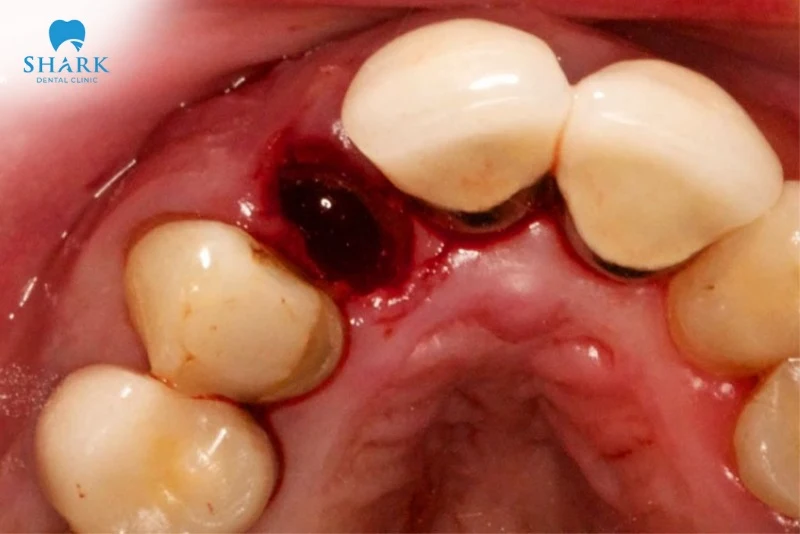

Tình trạng viêm ổ răng khô xảy ra khi cục máu đông này không hình thành, bị tan biến hoặc bong ra quá sớm thường trong 1-3 ngày đầu. Hậu quả là xương và dây thần kinh bị lộ ra môi trường khoang miệng, gây đau nhức dữ dội và chậm lành thương.

- Quan sát thấy xương trắng: Khi nhìn vào vị trí nhổ răng qua gương, thay vì thấy cục máu đông sẫm màu, bạn sẽ thấy một lỗ rỗng khô khốc, có thể nhìn thấy xương màu trắng xám bên trong.